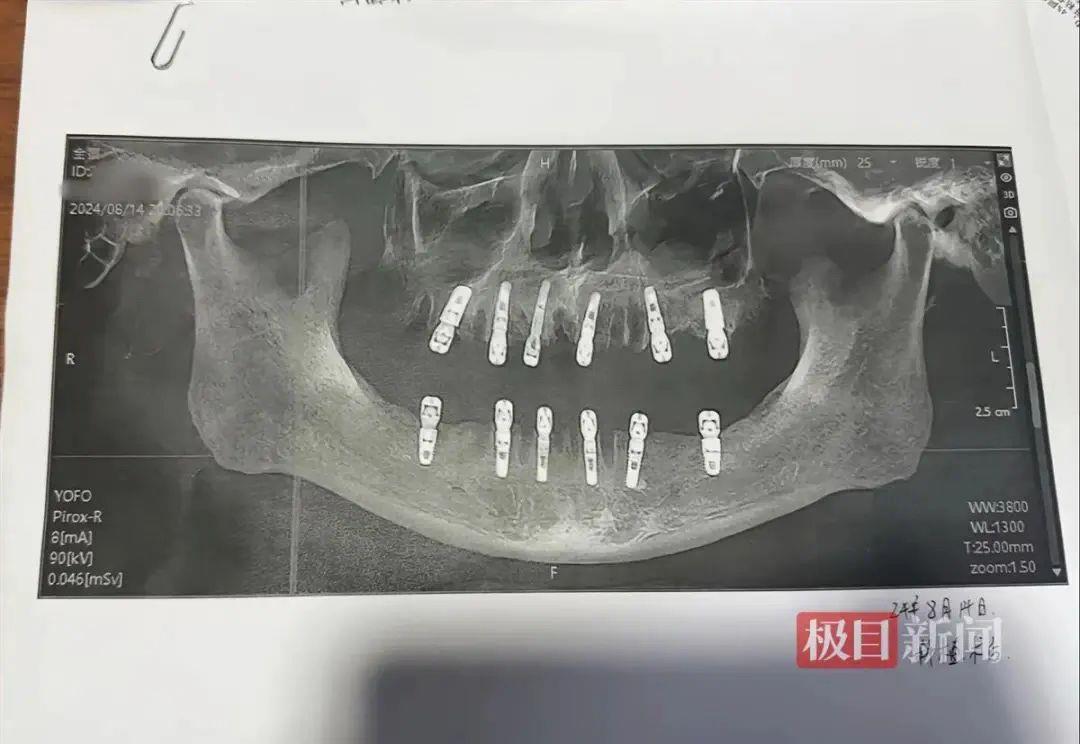

近日,浙江永康市一女士反映

其父亲在8月14日一天内

拔除23颗牙齿并种植12颗牙齿

随后疼痛不止,13天后死亡

当事人社交账号显示相关口腔影像资料。图源:极目新闻